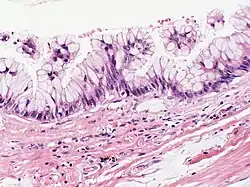

Mucinous cystadenocarcinoma

| Atypical goblet cells with focal tufting. The classification of these rare neoplasms is difficult and controversial. There appears to be a spectrum of mucinous cystic tumors ranging from those that are obviously benign (benign epithelium and no tumor invasion into surrounding lung) to those that exhibit invasion into surrounding lung tissue and are, therefore, malignant. In between is a group of neoplasms that exhibit epithelial atypia but no tumor invasion into lung tissue and the malignant potential of these is uncertain. This case appears to fall into that category. Focal cyst rupture with extravasation of mucin into surrounding lung tissue may occur with all types of mucinous cystic tumors. | |